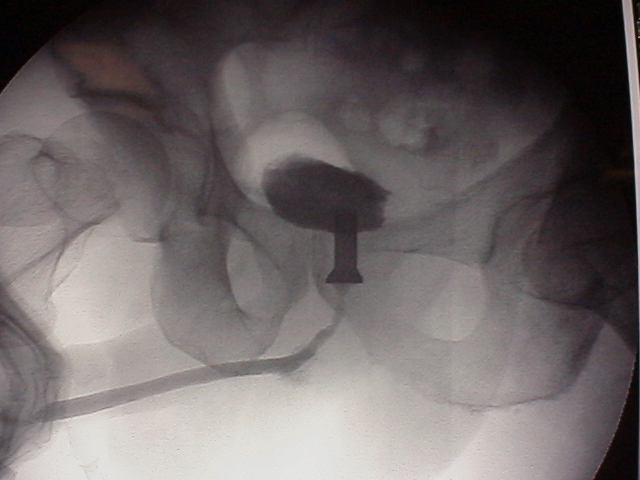

前立腺部尿道に留置したはずのコイルが、

膀胱内に落っこちる、というのはよくある話でした。